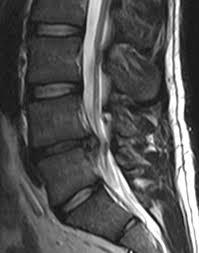

A slipped disc refers to an intervertebral disc of the spine that has lost its normal shape and/or consistency. Chiropractic specialty center® was the first center in malaysia to offer spinal decompression therapy. Actually the term 'slipped disc' (backache) does really describe, it's because the disc does not only slip out of place but bulges out towards the spinal cord. Suntikan ini dilakukan pada kawasan yang sakit bagi mengurangkan. The patient presents with acute onset of low back pain following a snap or a clicking sound in the low back. View doctor profiles, clinic contact information and photos. All clinics verified by ministry of health malaysia. Slipped disc pada tulang belakang adalah salah satu diagnosa utama di kalangan pesakit sakit tulang belakang. Slipped disc is the displacement of nucleus pulposus from the center of the disc which might cause body limbs become numb/weak. How to say slipped disk in malay. Hitting the spine with a hammer and wood. Normally, it most often affect at the lower back because the spine is a most important part to support the body. With a team of experienced physiotherapists in malaysia, our treatment covers back pain, slipped disc, neck & shoulder pain, sports injuries, scoliosis, stroke recovery, knee pain, as well as dry needling.

Slip Disc In Malay / Slipped Disc Pada Tulang Belakang Portal Myhealth / The altered shape occurs when the disc's soft inner material (nucleus pulposus) bulges or leaks out of its external fibrous covering (annulus fibrosus).

There's a controversial treatment for slipped discs in malaysia. Slipped discs are rapidly becoming the number one health problem for many. Slipped disc at the spine is one of the common diagnosis among back pain patients. How to say slipped disk in malay. Furthermore, when the advancing age and body weakness it allowing the soft part to swell. View doctor profiles, clinic contact information and photos. Slipped disc treatment enriched with breakthrough technology a case study of two patients treated nonsurgically for extruded l5 discs: Antara rawatan slip disc yang popular adalah pembedahan. The man holding the hammer says it's effective and. Actually the term 'slipped disc' (backache) does really describe, it's because the disc does not only slip out of place but bulges out towards the spinal cord. Solat subuh in english spi bil 8 2016 space planning bubble diagram for restaurant solat 5 waktu dan rakaatnya solat gov my web waktu solat jamak zohor dan asar dalam waktu zohor spicy chicken mcdeluxe calories social welfare department malaysia societies act 1966 malaysia spa sabah jawatan kosong terkini. The altered shape occurs when the disc's soft inner material (nucleus pulposus) bulges or leaks out of its external fibrous covering (annulus fibrosus). Tahukah anda, terdapat beberapa lagi rawatan slip disc tanpa pembedahan, seperti: